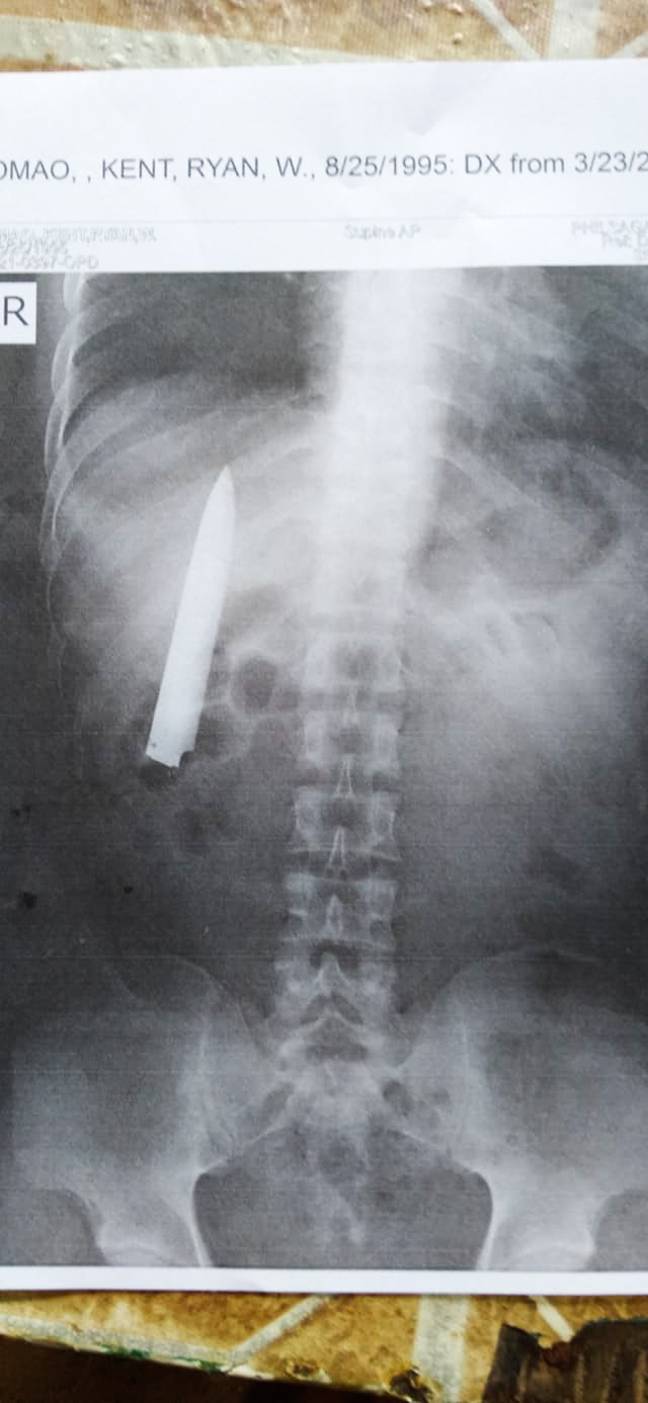

Ảnh chụp X-quang đã tìm thấy con dao hướng lên trên và mắc kẹt trong khung xương sườn của Kent - Ảnh: Viral Press

Bẵng đi hơn một năm, vào ngày 23-3 vừa qua, Kent kiểm tra sức khỏe để làm hồ sơ cho công việc ở hầm mỏ thì mới giật mình phát hiện một lưỡi dao dài hơn 10cm vẫn nằm bên trong ngực mình, tại vết thương năm xưa.